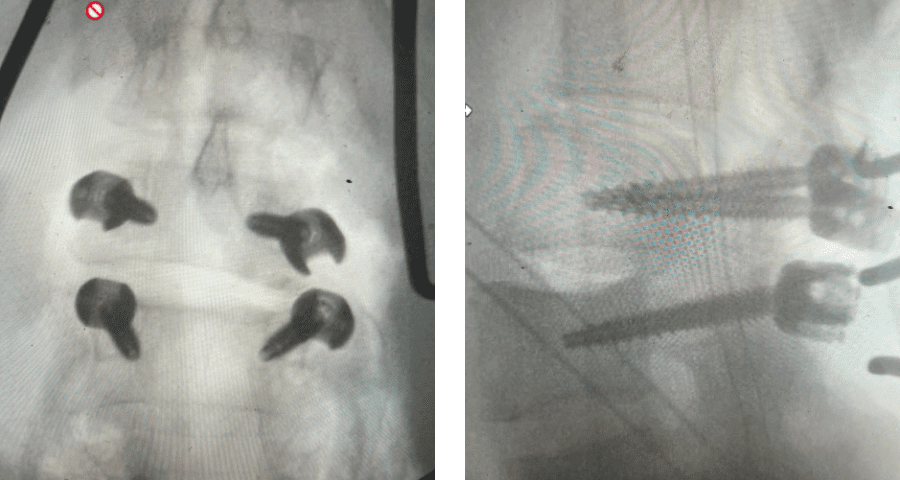

Revision surgery is more involved than primary surgery. In order to start decompressing this large complex, you must develop a plane; you have to find the edge of sometimes a remnant of a lamina or the lamina that can be buried in scar. You must carefully dissect the edge with a sharp upbiting curette and then either using a sharp Leksell to start removing this lamina or use a fine Kerrison to widen the plane and exposure and begin to expose the normal ligamentum above. In this case it was critical to expose and decompress the L3 nerve roots bilaterally. What is quite helpful is finding the inferior edge of the L2 facets. Then one must lift up the inferior L2 process up with a curette and simultaneously insert a Kerrison into joint space and remove the whole facet process. This is a great move because it allows access to the plane between the superior facet and the descending nerve root and a starting point to fully decompress the nerve root. Because of scarring there often is not a clear plane in order to accomplish the decompression. Care is taken to make sure there is a clear separation between edge of bone and dura during the process of inserting a Kerrison edge. The important part of this is feeling your opening and actually using your Kerrison as a dissecting tool once an edge has been established to perform a foraminotomy. We were able to remove the inferior L2 facet process with impunity as we knew we were performing an instrumented fusion to L2. The patient’s had a prior L3-5 instrumented fusion which upon exploration was solidly fused. It was decided to remove her prior hardware as it served its purpose and add a short segment from L2-3 (Fig 5). Patient did well after her surgery with relief of her right leg pain.

Fig 5: intraoperative fluoroscopic images demonstrating L2-3 screw placement.